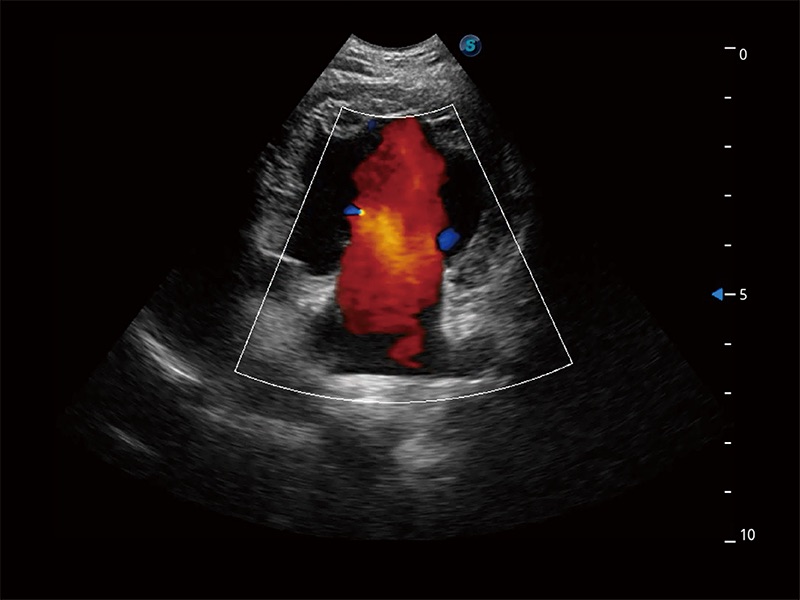

ProPet 80 配备了丰富的心脏探头群、先进的成像技术和专业的心脏测量工具,可帮助动物医生为不同体型和生理结构的动物提供心脏和心肌功能的全面评估。

实时用颜色表示心肌组织运动,观察和定量组织的运动情況,对快速检测与评估心肌的灌注和活性、电传导及心肌收缩和舒张功能等均能提供重要的诊断信息。

通过360度任意调节3条M型取样线,在同一心动周期上观察心脏不同位置的运动曲线,得到准确的心功能测量数据,有效评估心肌运动及左心室功能。